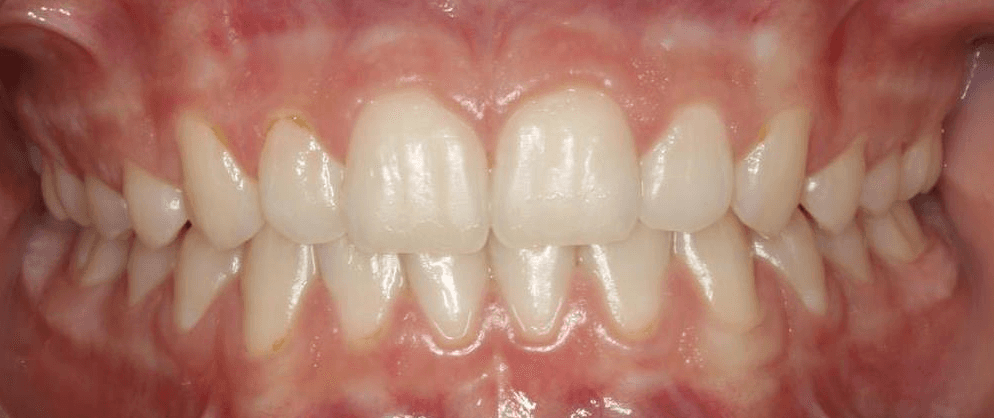

Final results

INTRAORAL